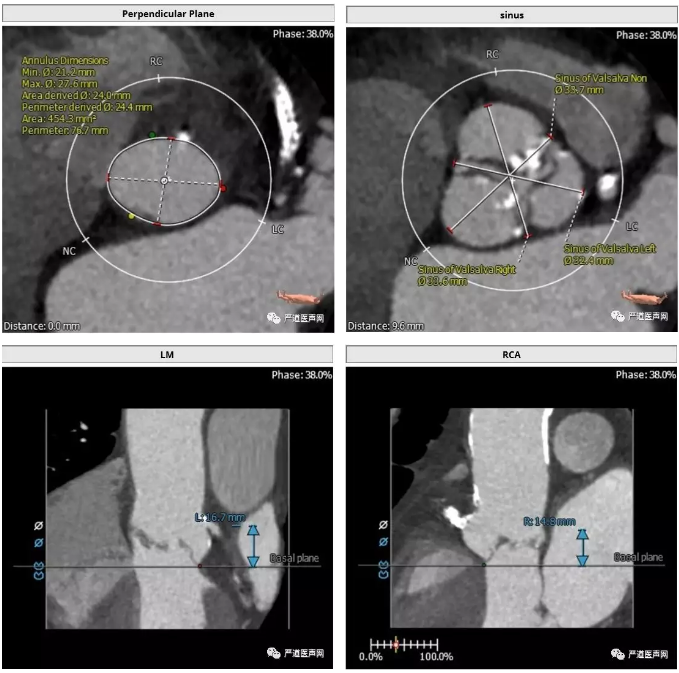

>>主动脉根部解剖:

三叶瓣,中度钙化,窦部结构尚可,冠状动脉高度尚可(LCA 16.7mm,RCA 14.8mm)。升主动脉弥漫性钙化,升主动脉高度40-50mm血管壁大量钙化并钙化中夹杂血栓,血管夹层风险较高。

根据患者术前 CT分析,这个病人瓣上 40-50mm 处主动脉弥漫性钙化,类似瓷化主动脉弓,钙化中夹有血栓,操作过程中主动脉夹层发生风险高。经术前讨论结合患者左室流出道解剖结构选择低位释放,规避升主动脉夹层风险,同时利用病人特有生理解剖结构规避术后瓣周漏的发生。同时根据四肢血管CT,选择右股动脉为主路径,选择 L29 规格VenusA-Valve 瓣膜。